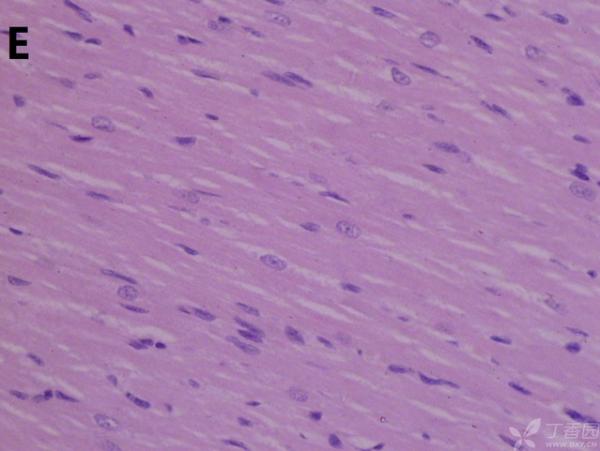

ÎÒ½«Ã¿¸ö×éÖ¯ÅÄÁË3¸öÊÓÒ°£¬ÒÔ±ã×ۺϷÖÎö£¬Âé·³¸÷λ°ïÎÒ°ÑA¡¢B¡¢C¡¢D¡¢E¡¢F¡¢GµÄËðÉË´óСÅŸö˳Ðò ÔÙ°ÑA¡¢B¡¢C¡¢H¡¢I¡¢JËðÉ˵ÄÑÏÖØ³Ì¶ÈÅŸöÐò¡£¸ÃÎÊÌâÒ²ÔÚ¶¡ÏãÔ°ÉÏÇóÖúÁË£¬Á´½Óhttp://www.dxy.cn/bbs/topic/23986562 A1.jpg A2.jpg A3.jpg B1.jpg B2.jpg B3.jpg C1.jpg C2.jpg C3.jpg D1.jpg D2.jpg D3.jpg E.jpg F1.jpg F2.jpg F3.jpg G1.jpg G2.jpg G3.jpg H1.jpg H2.jpg I.jpg I2.jpg I3.jpg J.jpg J2.jpg J3.jpg [ Last edited by ÀëÈËÏæÑÅÀá on 2012-10-9 at 21:11 ] |